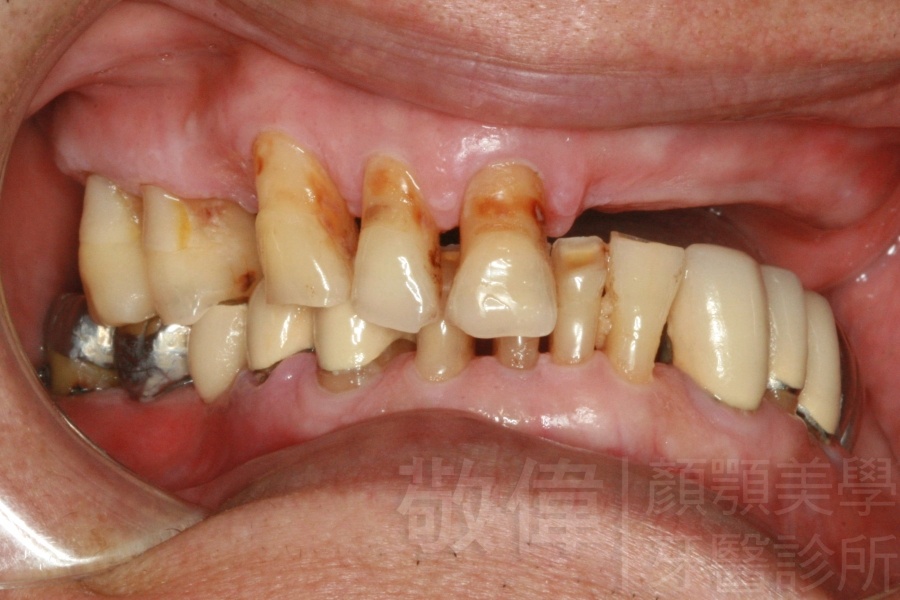

人工植牙/全口咬合植牙重建

治療前上顎   治療前正面   治療前下顎

治療後上顎   治療後正面   治療後下顎